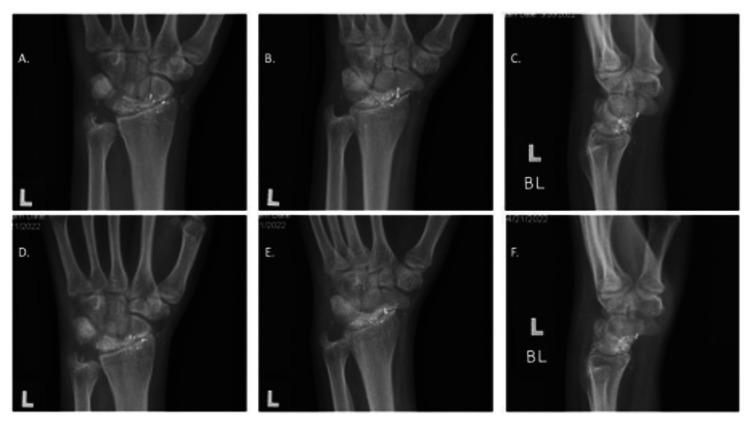

The incidence of non-fatal gunshot wounds has significantly increased in the past decade. The current guidelines lack clarity in treatment of bullet wounds to the hand and wrist. An 18-year-old male presented to the emergency department with a gunshot wound to the hand/wrist resulting in an open fracture. The entrance wound was clean without visible bone. No neurovascular damage was reported. The wound was irrigated with saline, and a sterile dressing and splint was applied in the emergency department. The patient was discharged the same day with oral antibiotics and an appointment with an orthopedic hand specialist. Three days after the injury, the patient was taken to surgery to treat a fracture of the radius and lunate. No internal fixation was required. The fracture and bullet fragments were removed, and the patient was discharged on the same day. The patient recovered to a full range of motion and no infection was acquired throughout treatment and healing.  The current guidelines for the treatment and management of nonfatal gunshot wounds to the hand and wrist are inconsistent resulting in unnecessary admittance to the hospital. Our paper provides a template for future cases allowing for outpatient treatment.

在过去十年中,非致命枪伤的发生率显著增加。目前的指南在手部和腕部枪伤的治疗方面缺乏明确性。一名18岁男性因手部/腕部枪伤就诊于急诊科,导致开放性骨折。入口伤口清洁,未见骨头外露。未报告神经血管损伤。在急诊科用生理盐水冲洗伤口,并应用无菌敷料和夹板。患者当天出院,带口服抗生素,并预约了手外科矫形专家。受伤三天后,患者接受手术治疗桡骨和月骨骨折。无需内固定。取出骨折块和子弹碎片,患者当天出院。患者恢复了全范围活动,在整个治疗和愈合过程中未发生感染。目前关于手部和腕部非致命枪伤的治疗和管理指南不一致,导致不必要的住院。我们的论文为未来病例提供了一个模板,允许门诊治疗。